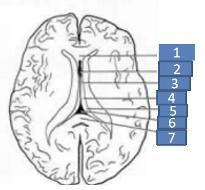

透明隔是两侧侧脑室中间的间隔,由两层垂直分割的薄板组成。在胎儿四个月时原始透明隔内形成一个中缝,然后发展为分离的两个小叶,两小叶之间的间隙即透明隔腔(cavum septum pellucidum,CSP)。

腔的前上方为胼胝体,后下方为穹隆。侧壁即透明隔小叶。透明隔腔≤3mm,描述可见透明隔腔,诊断甚至可不写。